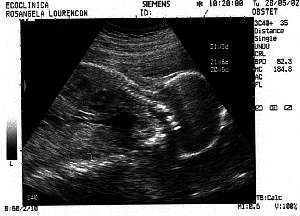

3rd Session - 28th May 2002

Week: 21

Size: Around

25 cm

Obs: IT'S A BOY !

Look this head. A genius :)

Laid back, hangin in there.